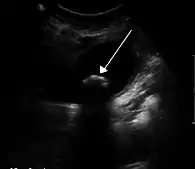

La colique hépatique est souvent liée à des calculs biliaires | |

On retrouve ce symptôme, par exemple, lors de l'expulsion d'un calcul hors de la vésicule biliaire (en même temps que la bile), lors de la contraction de celle-ci. Le calcul provoque une douleur vive en se déplaçant dans les voies biliaires : cette douleur peut irradier jusqu'aux côtes et l'épaule du côté droit.